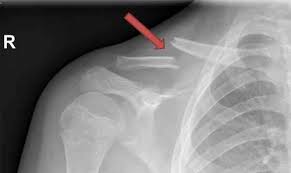

Eine erste Röntgenkontrolle sollte nach ca. Die meisten Brüche sind nach 12 Wochen stabil ausgeheilt. Selten wachsen die Bruchenden nach einer konservativen oder operativen Behandlung nicht richtig zusammen Pseudarthrose.

Die Reposition der Fraktur dh. Eine teilweise Metallentfernung am Sprunggelenk findet etwa sechs Wochen nach der Haupt-OP statt. Dauer der Therapie einer Schlüsselbeinfraktur Die Gesamtdauer der Therapie beträgt in der Regel 6-8 Wochen bei problemlosen Verlauf.

Nach einer Schlüsselbein OP wurde operativ ein Draht eingesetzt. Die Bewegungsfreiheit ist bei mir nach 8 Tagen wieder fast komplett hergestellt.

Nach rund 10 bis 15 Monaten sollte noch einmal eine Röntgenaufnahme durchgeführt werden und in diesem Zeitraum sollte mit dem behandelnden Arzt die Frage der Plattenentfernung erörtert werden.

Keiner kann sich das erklären da Patient 14 Tage nichts aktives gemacht hat was die Genesung beeinträchtigt. Dauer der Therapie einer Schlüsselbeinfraktur Die Gesamtdauer der Therapie beträgt in der Regel 6-8 Wochen bei problemlosen Verlauf. Nach rund 10 bis 15 Monaten sollte noch einmal eine Röntgenaufnahme durchgeführt werden und in diesem Zeitraum sollte mit dem behandelnden Arzt die Frage der Plattenentfernung erörtert werden. Ein Bekannter war bei seinem Schlüsselbeinbruch 50 Jahre alt und sollte den Verband 7Wochen tragen. Selten wachsen die Bruchenden nach einer konservativen oder operativen Behandlung nicht richtig zusammen Pseudarthrose. Woche kann die Schlinge abgelegt werden und der Arm ohne Gewichte bewegt werden. Muss bei einem operativ versorgten Schlüsselbeinbruch die Platte später entfernt werden. In manchen Fällen macht der Schlüsselbeinbruch aber eine Operation notwendig zum Beispiel wenn gleichzeitig die unter dem Schlüsselbein liegenden Blutgefäße oder Nerven verletzt oder die Knochenbruchstücke stark verschoben sind. Die meisten Brüche sind nach 12 Wochen stabil ausgeheilt.

Hier muss dann bei Beschwerden eine aufwendige Korrekturoperation erfolgen. Dauer der Therapie einer Schlüsselbeinfraktur Die Gesamtdauer der Therapie beträgt in der Regel 6-8 Wochen bei problemlosen Verlauf. Insgesamt ist beim Schlüsselbeinbruch mit einer Heilungsdauer von 6 bis 8 Wochen zu rechnen. Der Schmerzgrad Wunde nach der OP hält sich in Grenzen und kann mit handelsüblichen Schmerzmitteln gut kompensiert werden. Die Bewegungsfreiheit ist bei mir nach 8 Tagen wieder fast komplett hergestellt. Eine erste Röntgenkontrolle sollte nach ca. Hier muss dann bei Beschwerden eine aufwendige Korrekturoperation erfolgen.